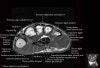

- Sagittal section

Sagittal T1 evaluates the tendons, bone marrow and relationships between the osseous structures.